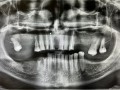

Rozległa torbiel zawiązkowa żuchwy

Paulina Adamska, Maria Mikołajska, Anna Janowska, Anna Starzyńska